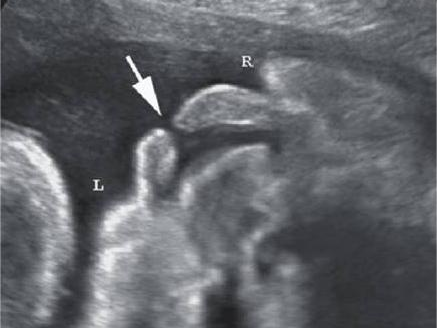

进行胎儿超声颈项透明层厚度(nuchal translucency,NT)检查,该检查利用超声测量胎儿颈后部皮下组织内积液的厚度,测值越大,染色体异常的风险越高。临床研究表明:胎儿NT厚度越高与罹患21-三体综合征、18-三体综合征、13-三体综合征等疾病的风险呈正相比。NT检查时还会检查胎儿的静脉导管(venous catheter,DV)频谱。相关研究显示:胎儿NT增厚及DV血流频谱异常都和先天性心脏病之间存在一定的联系。

先天性心脏病是胎儿时期发育不良引起的心脏结构异常,可能需要手术干预。

当进行胎儿超声筛查时,常见疾病专业知识是非常重要的。如果在检查中发现了左心室强光斑,这可能是胎儿存在某种心脏问题的迹象。在这种情况下,医生需要进一步观察和评估胎儿的心脏结构和功能,以确保任何潜在的问题得到及时的治疗和处理。如果发现了异常指标,比如颈部透明带过厚或者鼻骨缺失等情况,也需要引起警惕,这些指标可能表明胎儿存在染色体异常或其他遗传疾病的风险。医生会建议进一步进行遗传学检查,以确定胎儿的健康状况,并采取必要的措施来保护胎儿的健康。